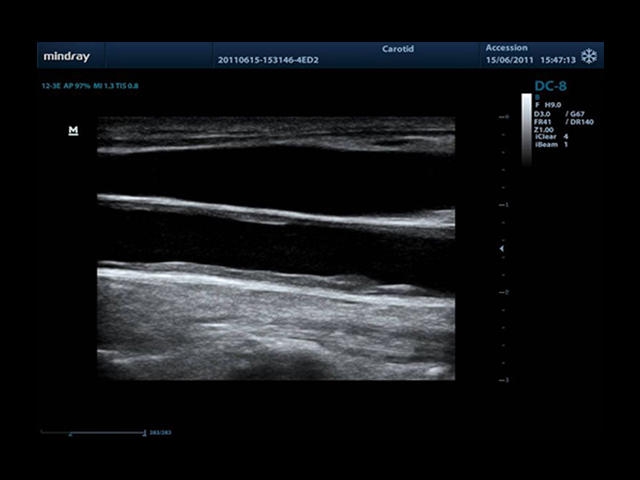

Mindray DC-8 Exp оснащен новым поколением датчиков с увеличенным количеством элементов и инновационной технологией "3T". Это позволяет достичь высокой детализации и качества изображения. Благодаря новейшей технологии iFlow, можно визуализировать даже самые мелкие сосуды и кровеносные пути.

• Auto IMT Package - измерения и анализ толщины комплекса интима-медиа (КИМ) сонной артерии.